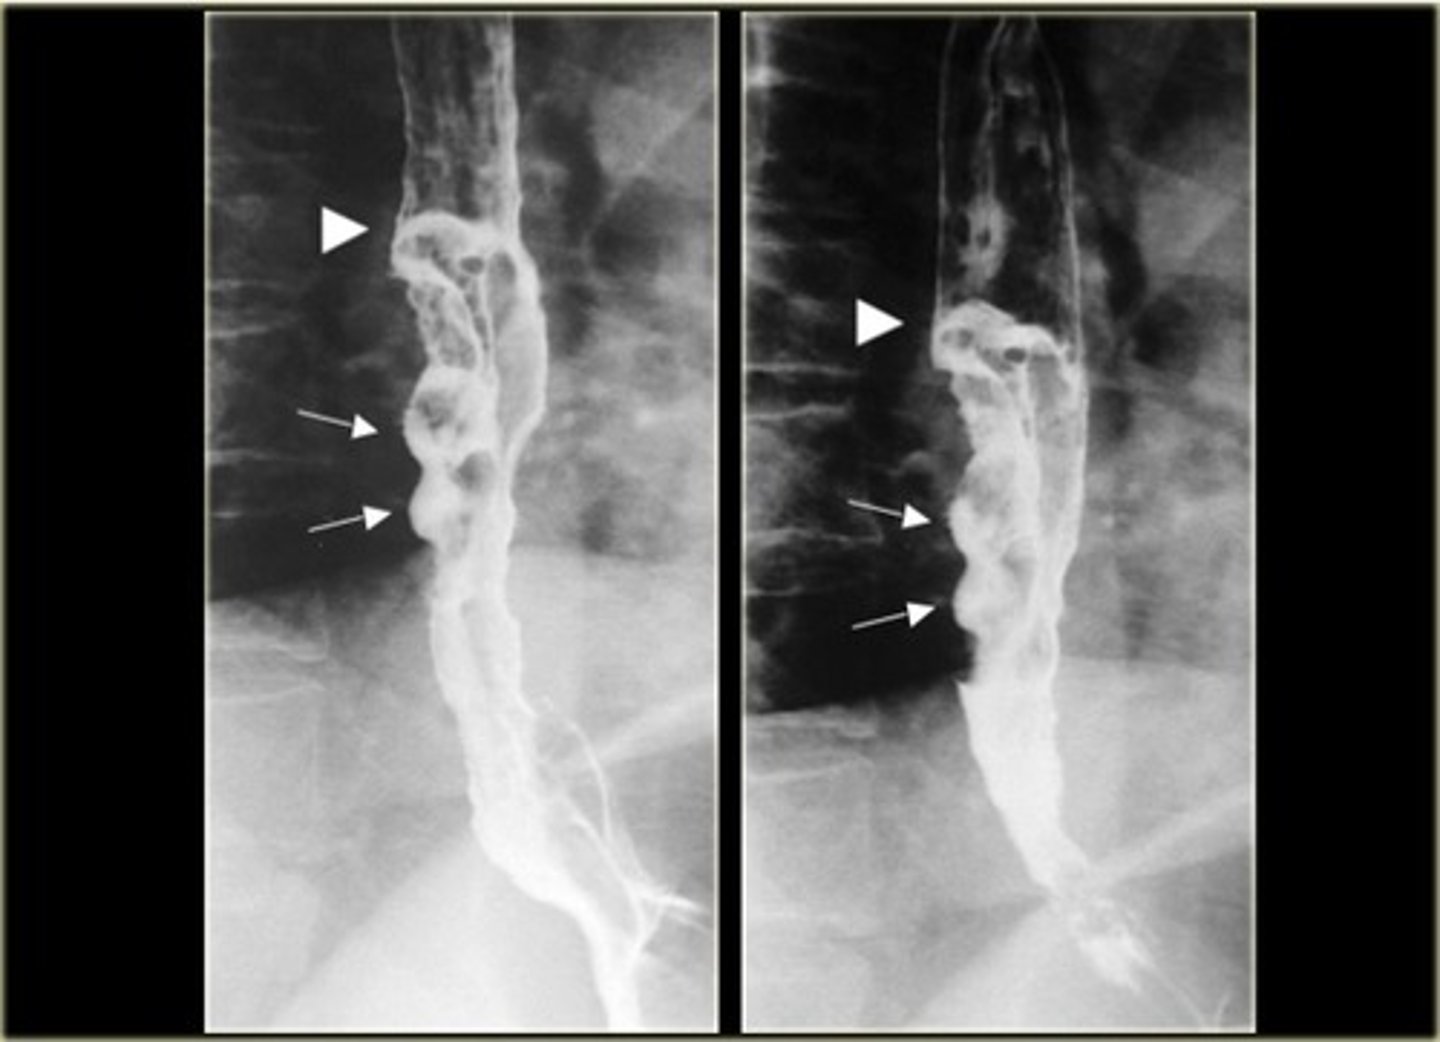

Achalasia

Achalasia (pic 5)

Achalasia (pic 2)

Achalasia (pic 3)

Achalasia (pic4 )